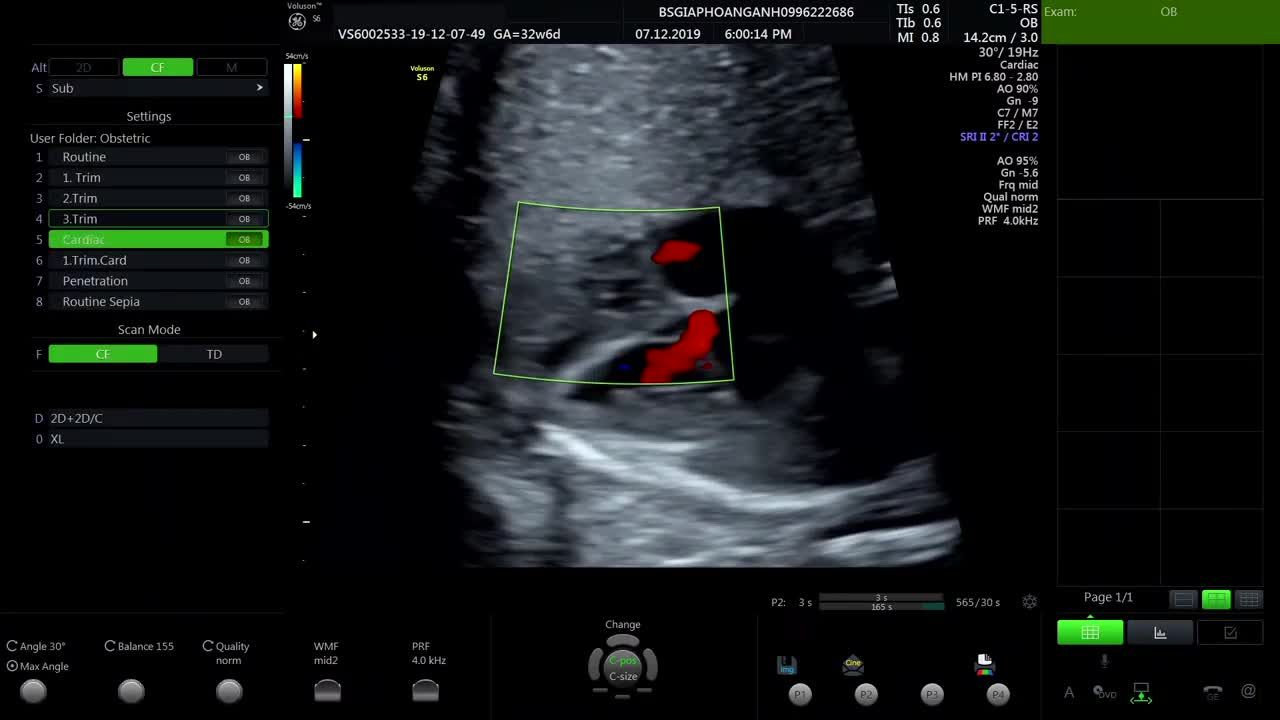

Siêu âm thai màng ngoài tim của bé có dịch có sao không?

Bác sĩ ơi, hôm qua em đi siêu âm thì bảo bé em bị màng ngoài tim có dịch. Nhờ bác xem giúp em với. Nếu mà bé cứu được thì sau này có để lại di chứng gì không ạ? Do em bé đầu nên không biết sao